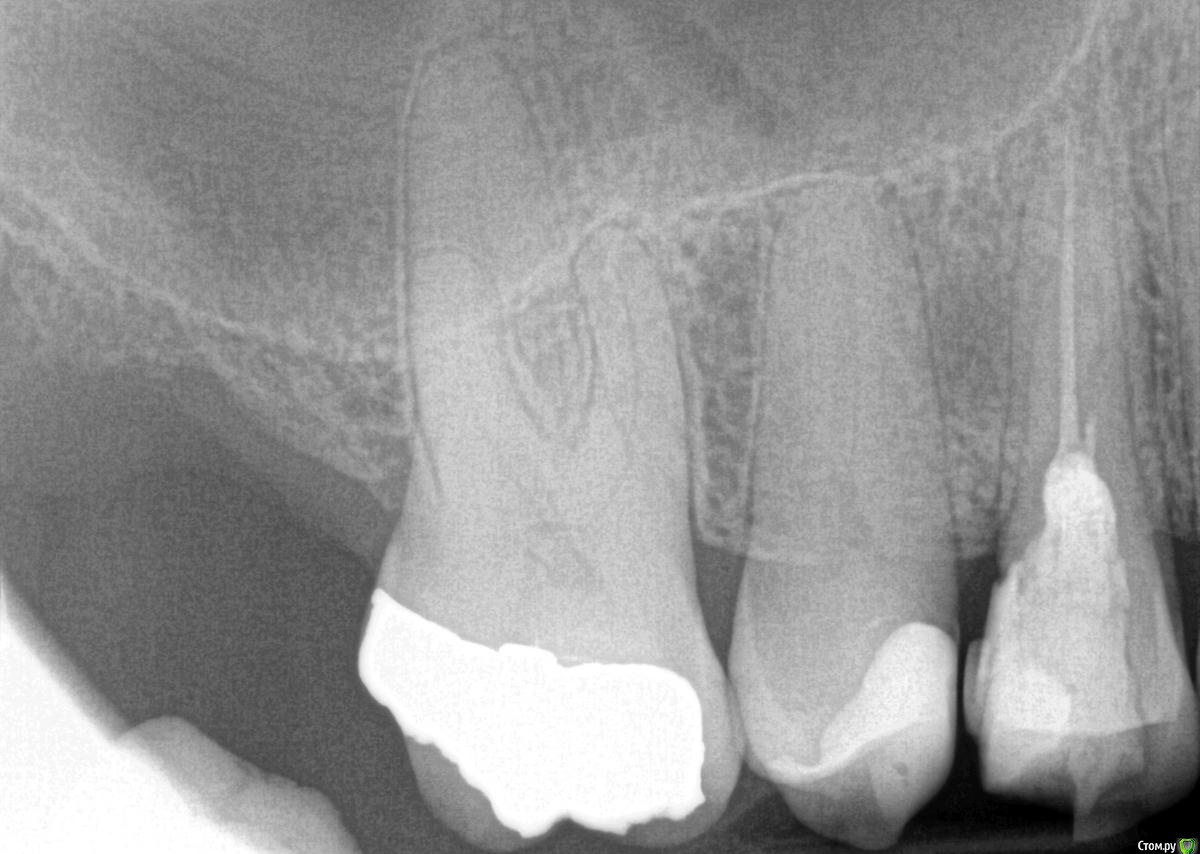

Rim3 Опубликовано 1 декабря, 2015 Поделиться Опубликовано 1 декабря, 2015 Уважаемые стоматологи, помогити пожалуйста! Во время пломбировки каналов верхнего бокового зуба с правой стороны у меня возникла резкая боль в районе синуса. Боль ушла через 3 -5 минут и врач настоял на продолжении лечения. Далее у меня опухла вся щека и появились синяки под глазами и щекой. Мне назначили стероиды и антибиотики. Как я позже поняла это было выведение гипохлорита натрия за пределы корня и травма. Теперь опухоль спала и синяки прошли. Я еще очущаю дискомфорт и некую болезненность в этой области.У меня теперь возник вопрос по поводу качества проведенного лечения каналов. Я собиралась закрыть зуб коронкой, но теперь сомневаюсь. Как вы считаете глядя на снимки, качественно ли запломбированы каналы? Что если не только гипохлотит натрия, но и гутаперча вышла за пределы корня. Возможны ли осложнения в будущем и операция по удалению лишнего материала? Ссылка на комментарий

anvladd Опубликовано 1 декабря, 2015 Поделиться Опубликовано 1 декабря, 2015 (изменено) Сделано хорошо,боли пройдут. Изменено 1 декабря, 2015 пользователем anvladd 3 Ссылка на комментарий

kozloff Опубликовано 2 декабря, 2015 Поделиться Опубликовано 2 декабря, 2015 Можно ли ставить коронку или лучше годик подождать? Ждать не нужно. За год зуб может треснуть пополам. Нужна культевая вкладка и коронка. 1 Ссылка на комментарий